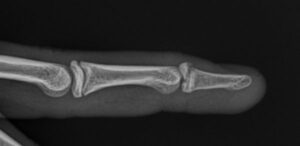

- Vrh prsta ostaje savijen (slika 1), može se opružiti pomoću druge ruke ali ne i zadržati u opruženom položaju.

- Savijen vrh prsta u „poslednjem“ – DIP zglobu, i ne može se opružiti aktivno